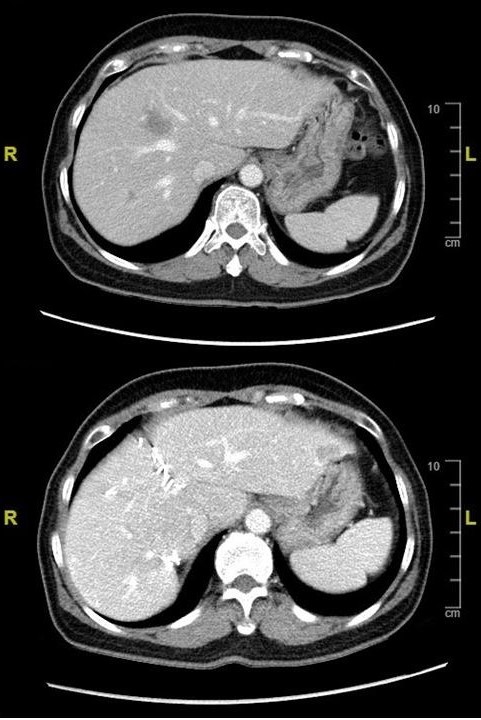

圖片說明:

2. 目前針對大直腸癌的肝臟轉移也建議以積極手術治療